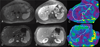

Magnetic resonance elastography (MRE) has been successfully implemented in the assessment of diffuse liver diseases. Currently, MRE is the most accurate noninvasive technique for detection and staging of liver fibrosis with a potential to replace liver biopsy. Magnetic resonance elastography is able to differentiate isolated fatty liver disease from steatohepatitis with or without fibrosis. Potential clinical applications include the differentiation of benign and malignant focal liver masses and the assessment of treatment response in diffuse liver diseases.